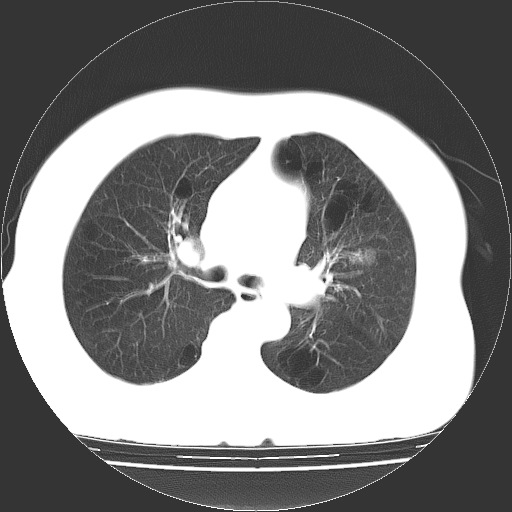

标题: CT13141:女,70岁,咳嗽、胸闷半个月。 [打印本页]

标题: CT13141:女,70岁,咳嗽、胸闷半个月。

女,70岁,咳嗽、胸闷半个月。纵隔窗未见异常,未上传。

小叶中心型肺气肿并多个肺大泡形成。

小叶中心性肺气肿及间隔旁肺气肿.(多与吸烟有关)

慢性支气管炎合并小叶中心性肺气肿及间隔旁肺气肿.(多与吸烟有关)。